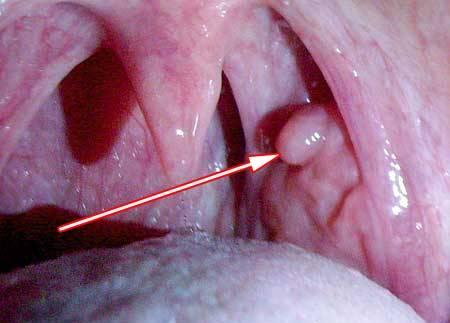

Важным компонентом диагностики является обследование врача-оториноларинголога. Во время осмотра врач внимательно изучает полость рта и горло пациента с помощью зеркала и инструментов. Папилломы на язычке в горле могут иметь различный внешний вид и располагаться на разных участках языка, поэтому при осмотре врач должен пристально обращать внимание на детали. Он может использовать бинокулярный лупу для более детального изучения патологического очага.

- Симптомы папиллом на язычке в горле: самый очевидный признак этого заболевания — наличие бородавчатых образований на язычке и в горле. Они могут быть белого или серого цвета и иметь цветовую неравномерность. Кроме того, могут наблюдаться симптомы, такие как затруднение глотания, боль и дискомфорт при разговоре и поедании пищи, кровоточивость при касании папилломы.